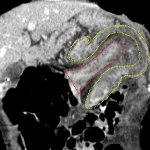

- Colo-colonic intussusception at the splenic flexure measuring 10 cm in length with a 3.5 x 2.5 cm mass at the distal margin of the intussusceptum

- Edematous appearance of the intussusceptum

- Malignant colo-colonic intussusception

Colo-colonic intussusception at the splenic flexure measuring 10 cm in length with edema and possible early ischemic changes of the intussusceptum. Mass at the distal margin of the intussusceptum is concerning for a neoplastic lead point. Recommend surgical evaluation.